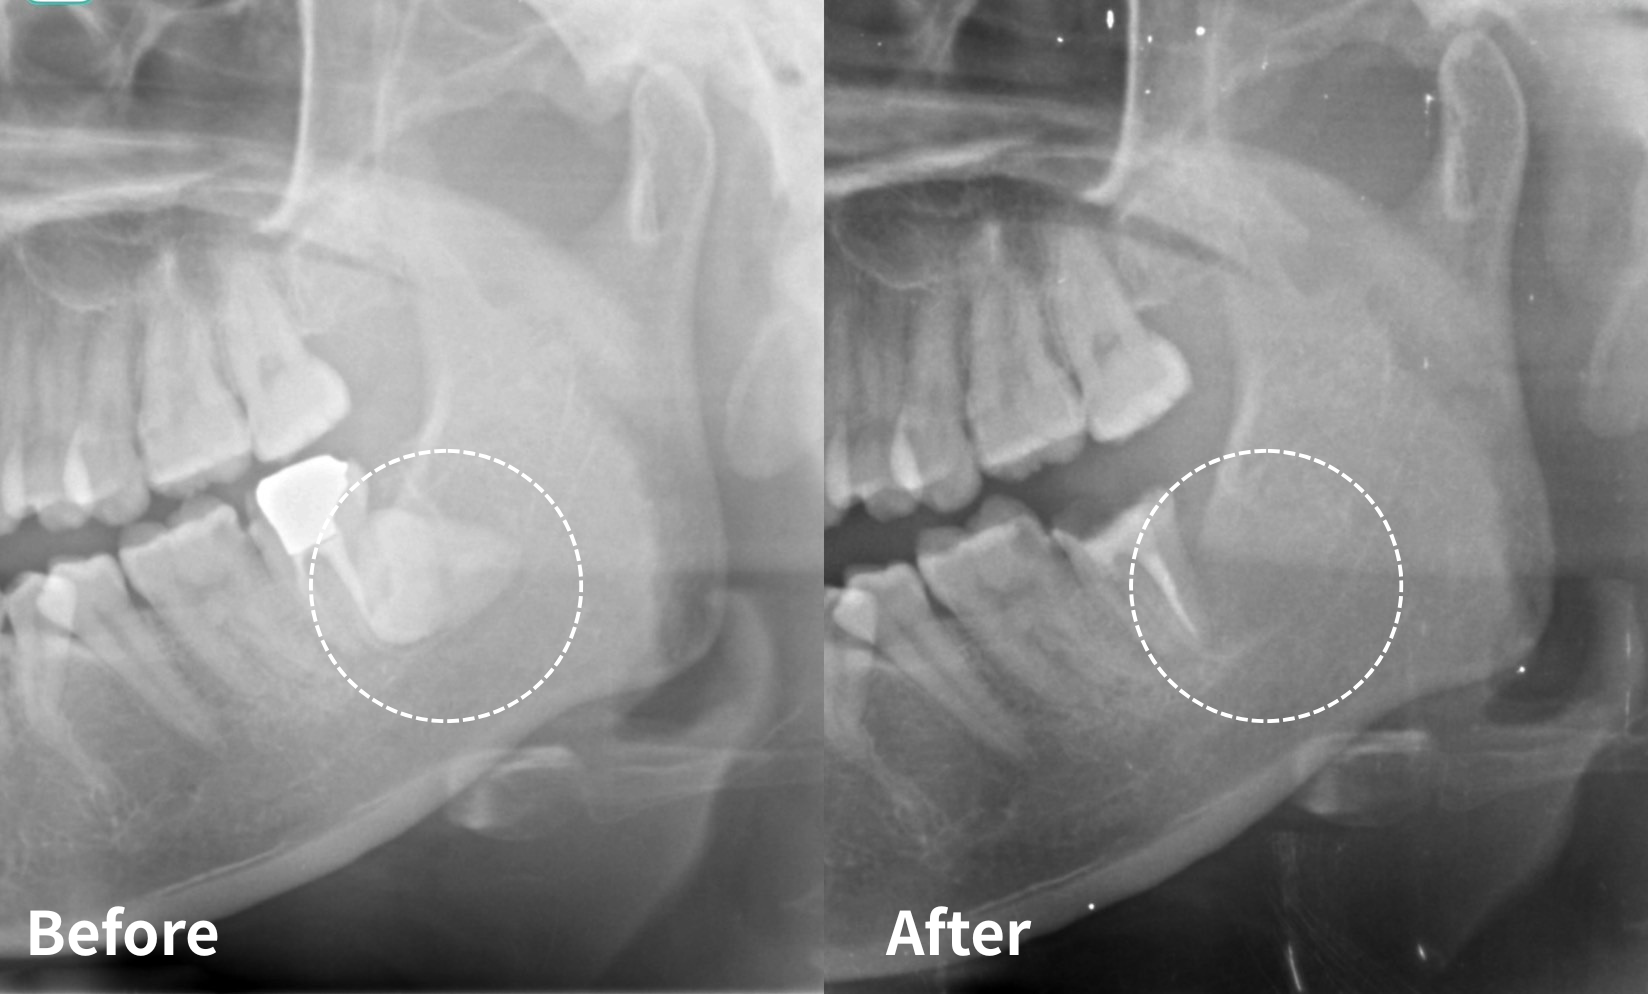

5. 矯正治療により機能的に活かせる場合

親知らずの位置や向きに問題がある場合でも、矯正治療により正しい位置に移動させることで、咀嚼に有効な歯として利用できるケースもあります。

たとえば、上顎の親知らずが前方に傾き、第二大臼歯とぶつかっていた場合、矯正によってその位置を整えることで、下顎の親知らずとの正しい咬合関係が得られることがあります。

※ただし、すべての症例において矯正が適応できるわけではありません。顎のスペースや歯の状態によっては移動が困難なこともあるため、事前に歯科医師の診断を受けることが大切です。